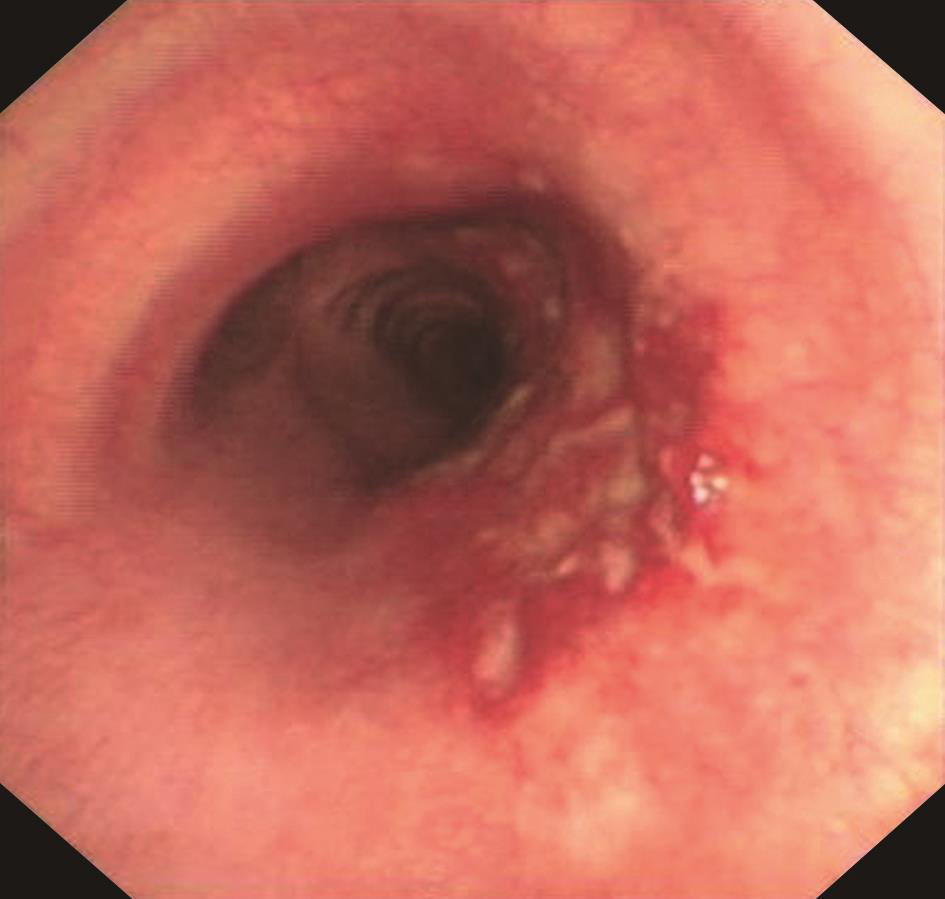

电子支气管镜检查(2016年2月2日):

支气管镜下见气管黏膜糜烂(图2)。右中间支气管黏膜活检病理示支气管黏膜慢性炎症,鳞状上皮增生,黏膜糜烂坏死,肉芽组织增生,间质大量急慢性炎症细胞浸润,并见多核巨细胞反应(图3),刚果红染色阳性,抗酸染色阴性。

图2 支气管镜下见黏膜糜烂

图3 右中间支气管黏膜活检病理(HE染色,×100)